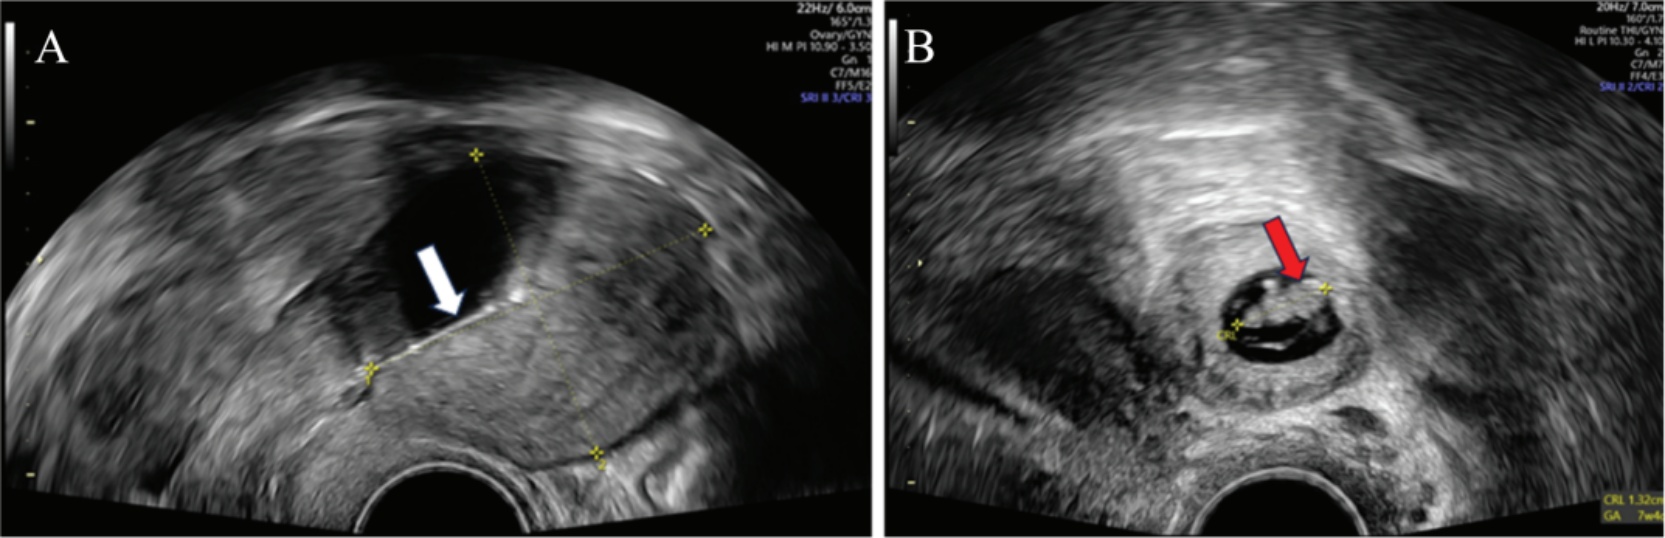

Figure 5. POCUS demonstrates the following findings: (A) an intrauterine device (white arrow); (B) an ectopic pregnancy (red arrow) at a gestational age of 7 weeks and 4 days. CRL, crown-rump length; GA, gestational age

5. POCUS显示,(A) 宫内系统(白色箭头);(B) 异位妊娠(红色箭头),孕周为7周加4天。CRL,头臀长;GA,孕龄